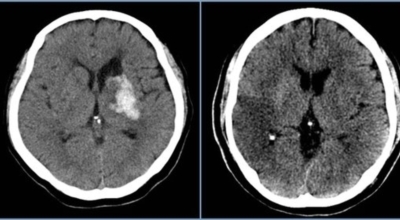

뇌출혈 전조증상을 놓쳐 뇌출혈이 발생하게 되면 발작 직후 안정을 취해야 합니다. 뇌부종을 가라앉히기 위해 약물 요법으로 고농도 포도당, 덱사메타존, 만니톨 등을 투약할 수 있고 뇌의 혈액 순환을 회복시키는 주사와 지혈제, 진정제 등을 사용할 수 있습니다. 혈종의 크기가 중등도 이상으로 마비 증세가 있으면 머리뼈에 작은 구멍을 내서 관을 넣어 혈종을 뽑아내는 수술을 시행할 수 있습니다.

혈압성 뇌출혈인 경우 혈종의 크기가 작으며 환자의 증상이 경미하면 약물 치료를 시행합니다. 혈종의 크기가 매우 크며 뇌가 심하게 부어오를 때는 응급으로 머리뼈를 절개해 혈종을 빠르게 제거해야합니다. 응급조치가 늦어지면 뇌압이 상승해 의식을 잃고 사망에 이를 수 있기 때문인데요 이렇게 증상이 심할 때는 수술이 잘 되었더라도 예후가 좋지 못할 때가 많다고 합니다.